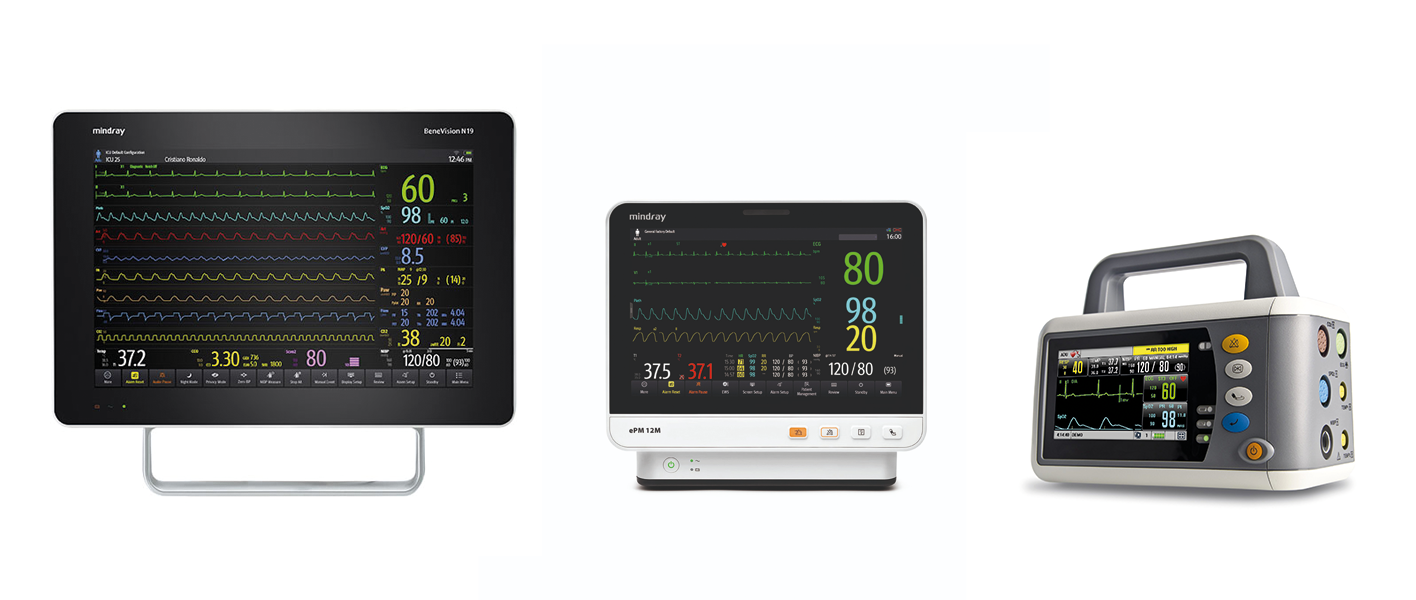

Стационарный – как правило, это большой дисплей (19" и выше), основной корпус, не имеет ручки для переноски и крепится обычно на стену или консоль.

Компактный – может использоваться как стационарно, так и для переноски.

Транспортный – компактный форм-фактор с наличием транспортных сертификатов, ударо- и влагоустойчивый.